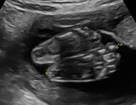

Differenzierte Fehlbildungsdiagnostik

Diese weiterführende feindiagnostische Untersuchung wird zwischen der 20. – 24. Schwangerschaftswoche durchgeführt.

In der Regel wird für diese Untersuchung eine Überweisung vom betreuenden Frauenarzt ausgestellt, z. B. wenn im Rahmen der üblichen in den Mutterschaftsrichtlinien empfohlenen Ultraschalluntersuchung eine Auffälligkeit gesehen wurde. Weitere Gründe für eine Überweisung sind Risikoschwangerschaften oder auch der Wunsch der Eltern nach einer zusätzlichen Absicherung. Neben der allgemeinen Entwicklung des Kindes können hier –noch genauer als im Ersttrimesterscreening – alle Organe des ungeborenen Kindes begutachtet werden. Zusätzlich wird mittels Dopplersonographie die kindliche Versorgung und die des Mutterkuchens überprüft. Da Herzfehlbildungen zu den häufigsten angeborenen Fehlbildungen gehören, stellt die detaillierte fetale Echokardiographie (Untersuchung des kindlichen Herzens) einen wichtigen Bestandteil der Untersuchung dar. Dabei werden sowohl die Anatomie des Herzens als auch die Blutflüsse begutachtet.

Organfeindiagnostik